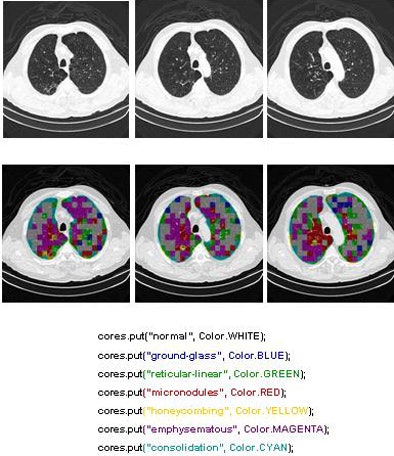

Two of the nine classes, background and outside tissue, indicate regions outside the lungs. The remaining seven classes refer to patterns found in the lungs: normal parenchyma, ground-glass opacities, reticular and linear opacities, nodular opacities, honeycombing, emphysematous change, and consolidation.

In the last step, postprocessing, each pattern type is assigned a color label and the DICOM file is rebuilt. The communication/archiving agent finishes off the process by including the image slices with the labeled ROIs as a new image series in the exam and sending it back to the PACS server. The color coding allows radiologists to easily see which lung regions might be affected by a particular type of diffuse lung disease.

| The completed CAD-analyzed cases are stored as a new series in the PACS server, where they can be examined side by side. In the color-coding system, normal parenchyma is white; ground-glass regions are blue; reticular-linear, green; micronodules, red; honeycombing, yellow; emphysematous changes, magenta; and consolidation, cyan. |